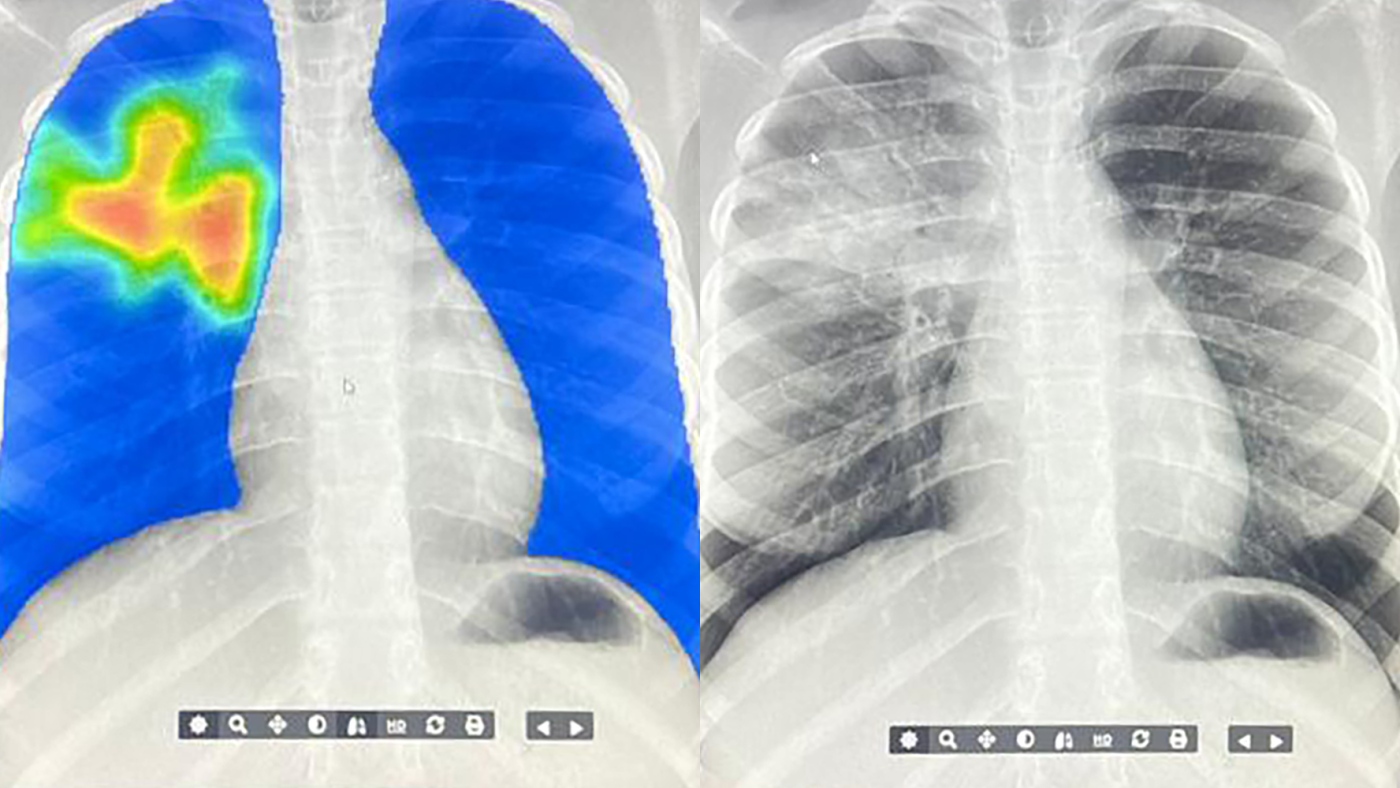

AI steps in to detect the world's deadliest infectious disease

There’s a global shortage of radiologists. Now artificial intelligence is helping speed up the diagnosis of tuberculosis in hard-to-reach communities. (Image credit: ARCAD Santé PLUS) Source link